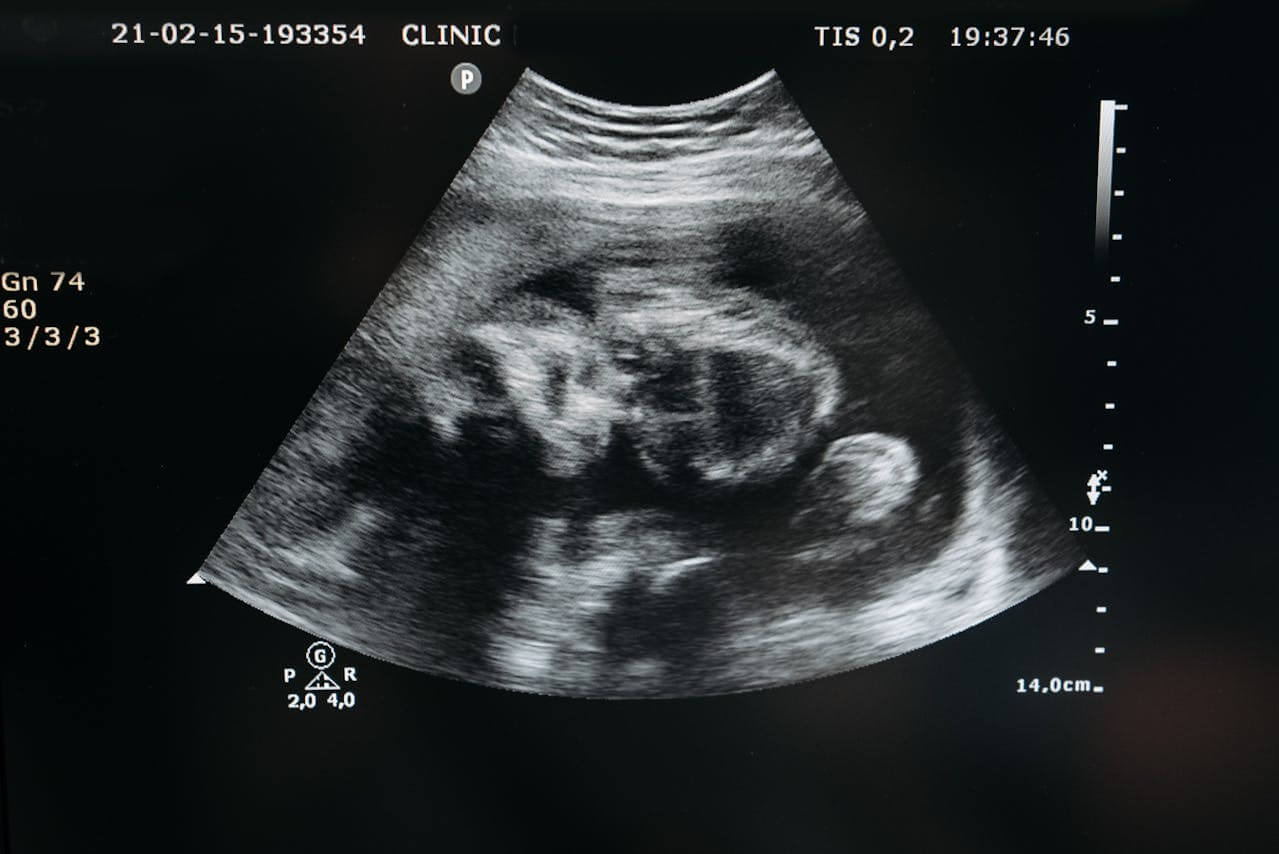

Buat sebagian besar orang, USG atau ultrasonografi seringkali hanya mengaitkannya dengan kehamilan. Tidak heran karena hampir setiap ibu hamil menjalani pemeriksaan USG untuk melihat perkembangan janin. Namun sebenarnya, fungsi USG jauh lebih luas daripada sekadar memantau kandungan.

USG yang menjadi salah satu teknologi pencitraan medis yang paling aman, cepat, dan praktis. Sayangnya ini menjadi persepsi umum masih menyempitkan kegunaannya. Padahal kenyataannya USG yang merupakan alat diagnostik serbaguna yang bisa memanfaatkannya untuk berbagai kondisi medis, tidak hanya kehamilan.

Popularitas USG sebagai bagian dari pemeriksaan kehamilan memang sangat tinggi. Hampir semua ibu hamil menjalani USG berkala, sehingga masyarakat terbiasa menganggap USG sebagai "alat untuk melihat bayi". Padahal, dokter menggunakan USG setiap hari untuk membantu diagnosis berbagai penyakit lainnya.